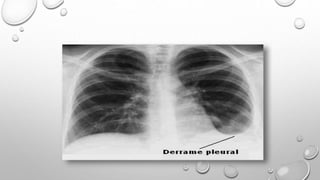

Sinais No

Raio- x

Setas indicando Sinal de Menisco.

Típico em derrame Pleural